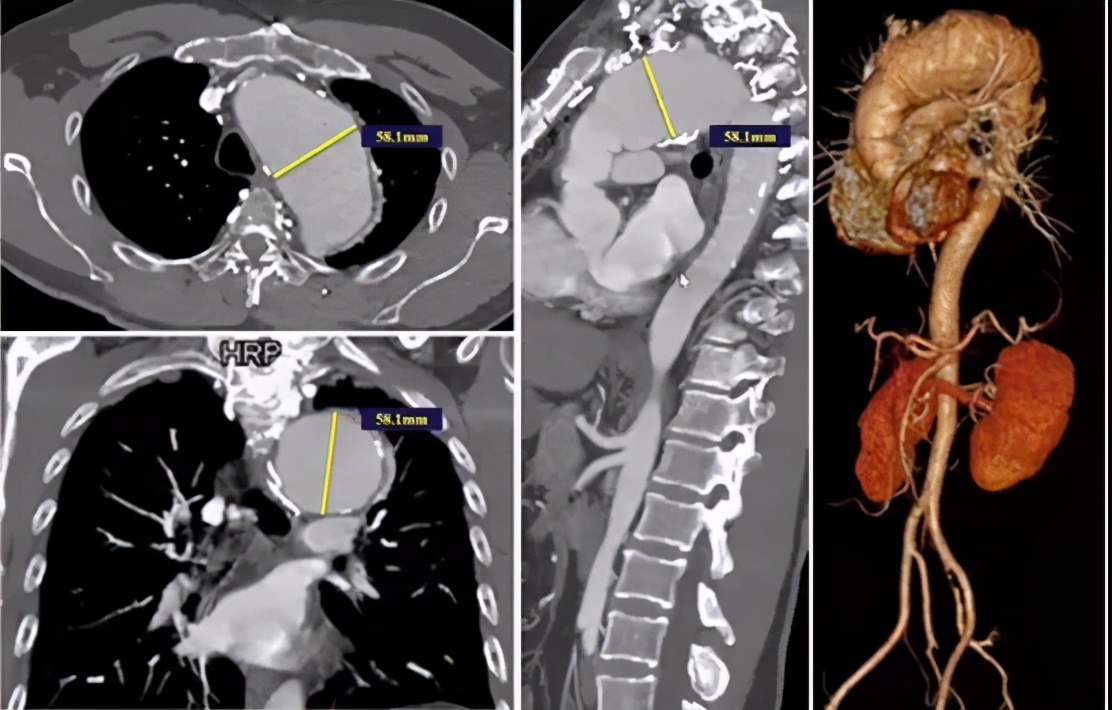

病例3(男性,70岁)

主诉:发现主动脉弓部瘤1天。

既往史:高血压。

手术史:16年前因“升主动脉瘤+AI(重度)”行Bentall手术;6月前行白内障手术。

手术关注点:病变部位邻近LCCA,单纯覆盖LSA锚定区不足。IA、LCCA共干,如何重建?避免远期裸支架损失升主动脉壁的风险。

手术方法:IA、LCCA预开窗+LSA原位开窗+主动脉腔内修复术(锚定于升主动脉人工血管内)。

手术步骤:无名动脉、左颈总动脉体外预开窗;释放远端限制支架+近端主体支架;LSA原位开窗+支架植入。